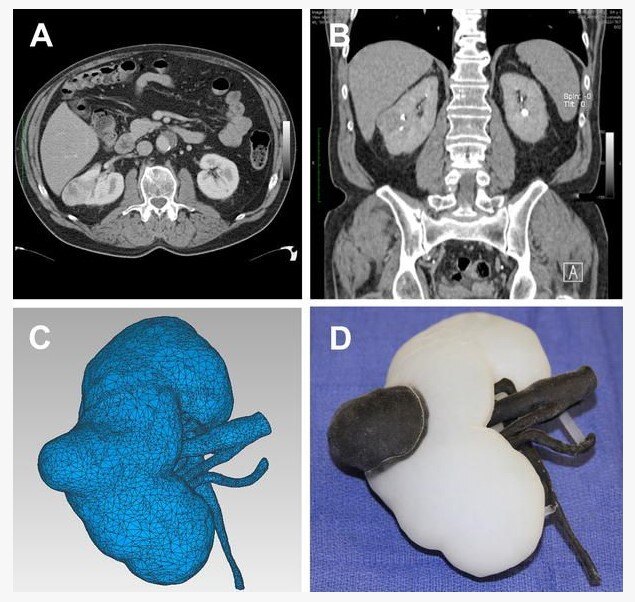

3.术前3D打印模型应用

肾肿瘤3D打印模型比三维图像更直观的给手术医生局部的细节,对于体积,接触面积,切除角度等非常精准判断,可以帮助减少术前的误判。有利于手术医生制定在模型上进行推演,制定最佳手术方案并验证方案可行性。对需要精准三维判断,缩短手术时间、出血少术后并发症少保肾手术来说获益良多。缺点是定制需要一定的时间,成本略高。